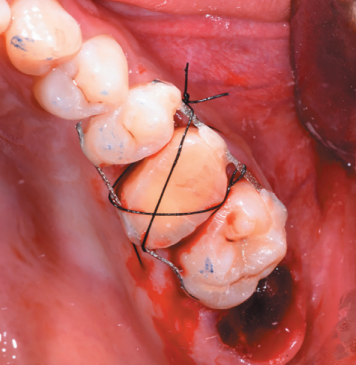

After reducing the occlusion, a cross stitch with monofilament suture (AragoTM, Barcelona, Spain) was applied around the transplanted tooth to increase its fixation (Figure 13), performing an intraoperative periapical radiograph with parallelism technique (Figure 14).

2.8 transplanted in the alveolus of the 2.6.